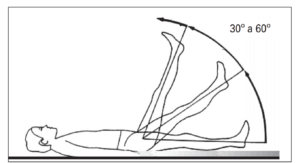

O exame físico no consultório poderá trazer informações importantes, como a manobra de Lasegue ou a perda do reflexo calcâneo com a percussão.

Manobra de Lasegue:

Elevasse passivamente a perna do paciente, geralmente até 30-40 graus e a dor que o paciente sente aparece no exame físico.

Manobra de Lasegue utilizada no exame físico para demonstração de acometimento neurológico.